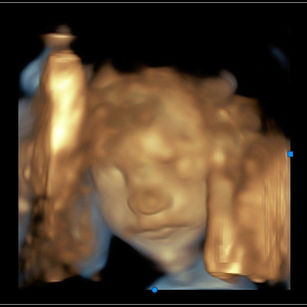

24 Weeks 1 Day Pregnant

Weight: ~1.25 pounds (0.56 kg), the size of an Ear of Corn!

Length: ~12 inches (30.5 cm)

Development Highlights:

Lungs developing more complex airways; surfactant begins forming.

Brain growth accelerates; neurons forming rapidly.

Taste buds fully formed.

Skin is still translucent; vernix caseosa starting to cover more of the body.

Movements: Stronger kicks, flips, and stretches. You may feel patterns of activity.